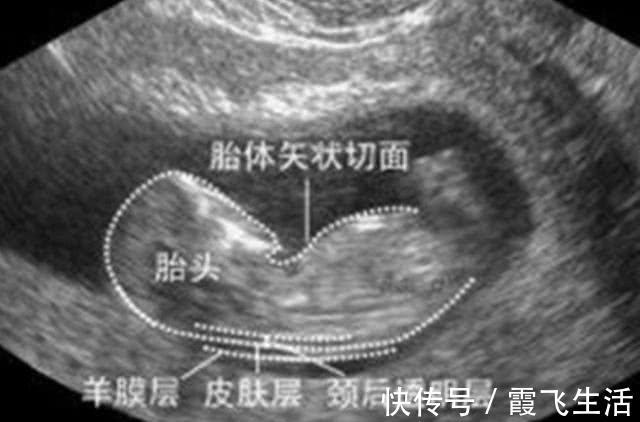

是nuchaltranslucency的简称,是指颈后透明层,即胎儿颈椎水平面皮肤到皮下软组织间的厚度。

它是目前一种通过B超手段来测量胎儿颈部皮下无回声透明层最厚部位的厚度,以此来评估胎宝宝是否患有唐氏综合征。